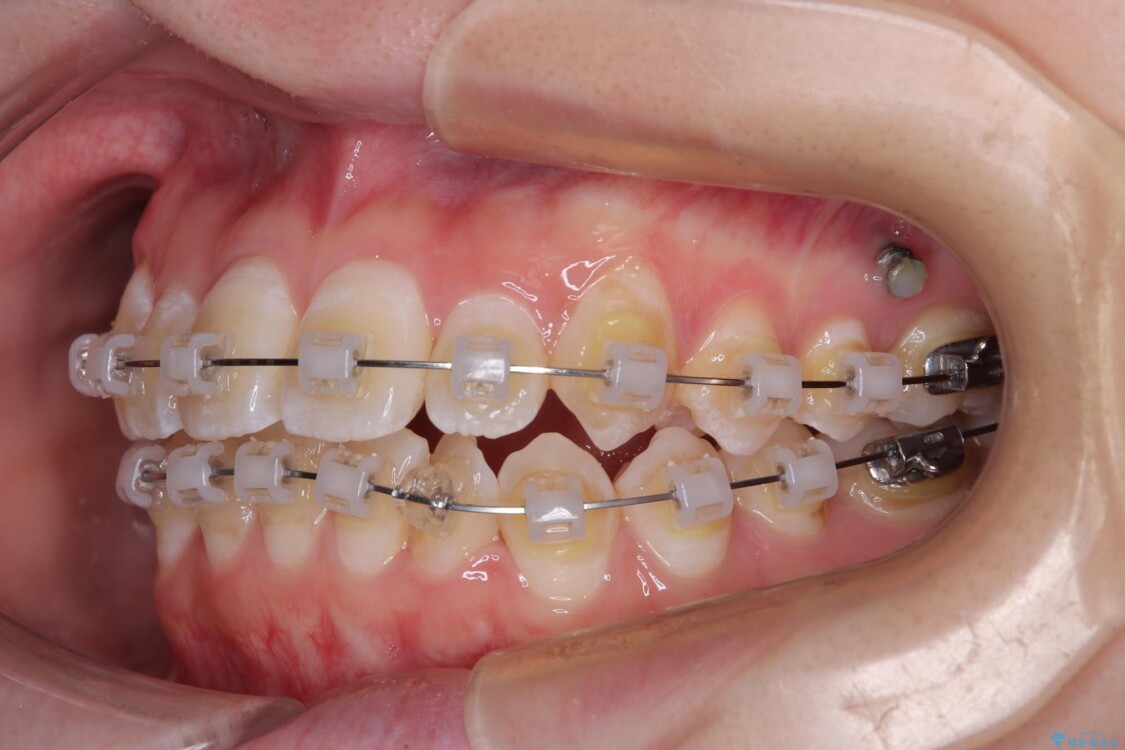

治療途中

• 【モニター】前歯のデコボコをスッキリ解消!目立ちにくいワイヤー矯正でスピーディに治療完了 治療途中画像

マウスピース矯正も検討されていましたが、「装着時間の自己管理が難しそう」「なるべく早く治療を終えたい」とのご希望から、ワイヤー矯正を選択されました。

目立ちにくさと費用のバランスを考慮し、プラスチックブラケット+メタルワイヤーを採用。日常生活でも装置の存在感を気にせずお過ごしいただけます。